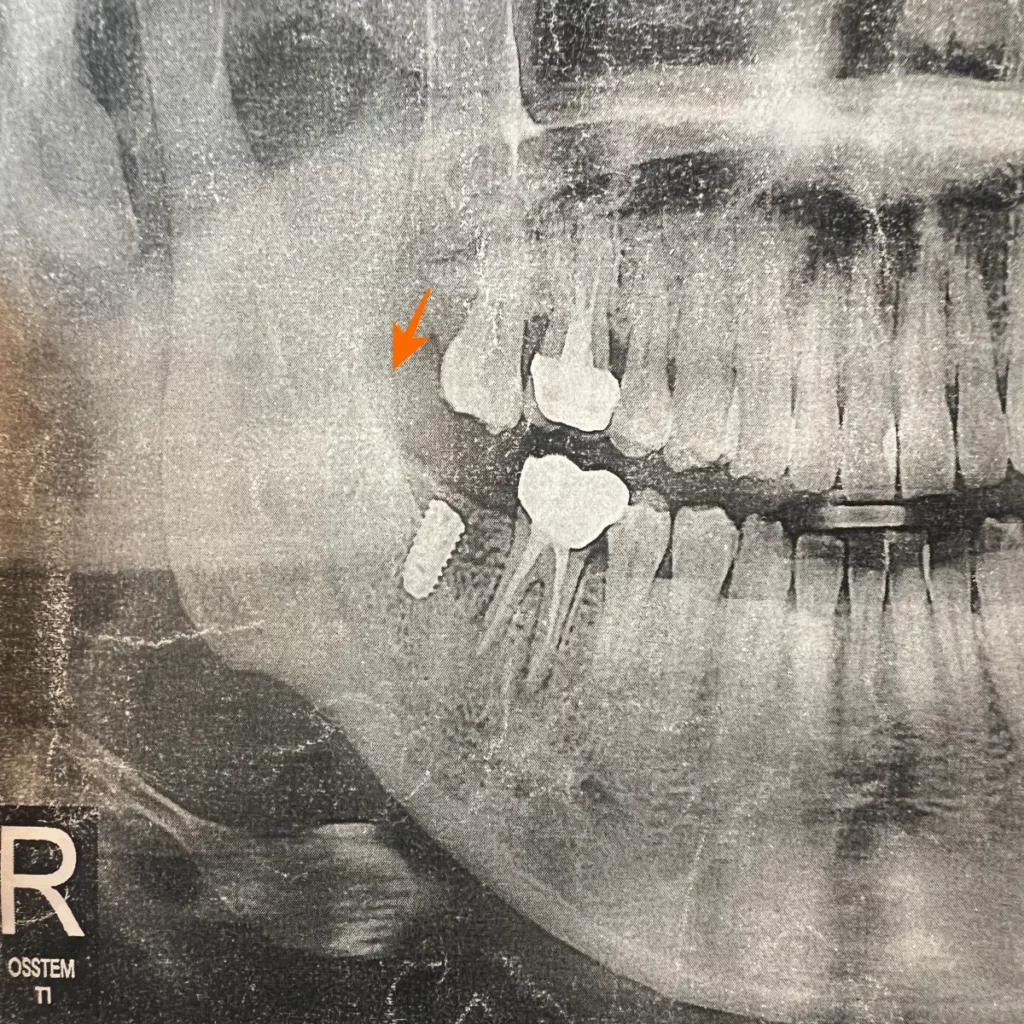

아래 치아를 발치하고 너무 오랜 시간이 지난 상황이라 위 치아가 내려온 상황이었어요.

이렇게 되면 나중에 임플란트를 다 했을 때 위 치아와 교합이 맞지 않아서 부정교합이 생긴다고 말씀하셨는데요. 따라서 치아와 잇몸, 턱관절에 문제를 일으킬 수 있기 때문에 내려온 위 치아를 깎아내야 한다고 하셨어요.

저는 발치 후 5년이라는 세월이 지났기 때문에 어느 정도 이 점을 각오하고 치과에 갔었는데 사진을 찍어보니 잇몸뼈 상태가 괜찮다고 하셔서 정말 다행이었어요. 하지만 안 좋은 상황은 언제든지 발생할 수 있으니 이 점 유의하셔야 해요!